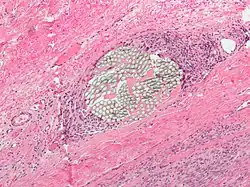

Giant cell arteritis

Giant cell arteritis,[6] also known as temporal arteritis or cranial arteritis, is the most common MGC-linked disease. This type of arteritis causes the arteries in the head, neck, and arm area to swell to abnormal sizes. Although the cause of this disease is not currently known, it appears to be related to polymyalgia rheumatica.[7]

Giant cell arteritis is most prevalent in older individuals, with the rate of disease being seen to increase from age 50. Women are 2–3 times more likely to develop the disease than men.

Diagnosis

The current highest standard for diagnosis is a temporal artery biopsy.[12] The skin on the patient's face is anesthetized, and an incision is made in the face around the area of the temples to obtain a sample of the temporal artery. The incision is then sutured. A histopathologist examines the sample under a microscope and issues a pathology report (pending extra tests that may be requested by the pathologist).